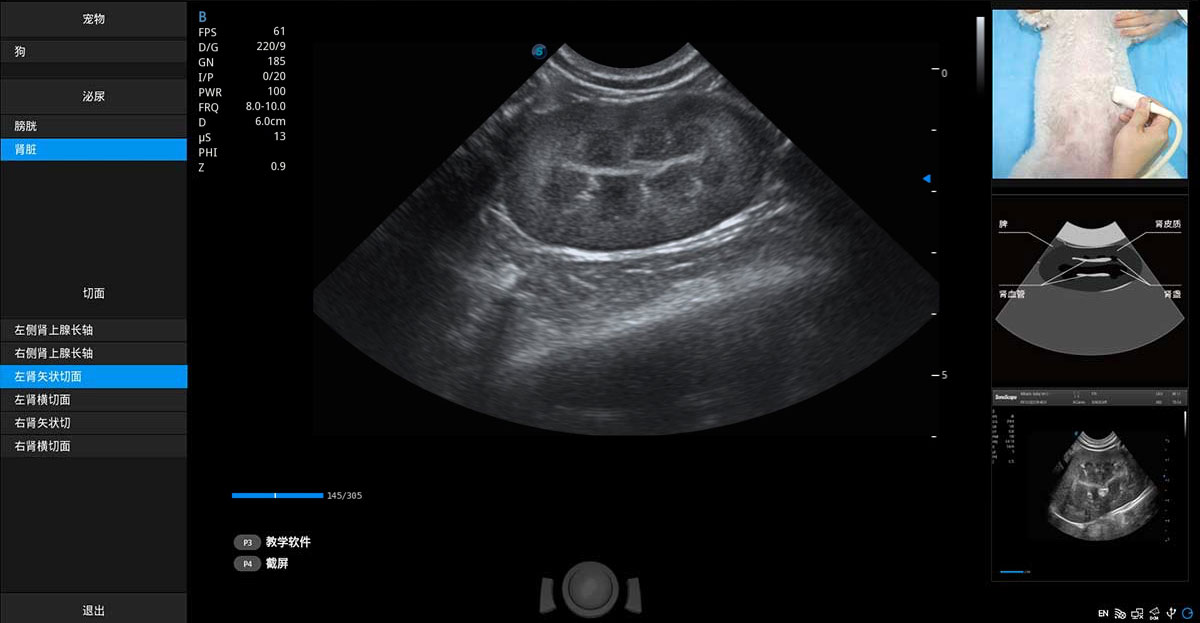

ProPet 70專為動物醫(yī)生設(shè)計(jì),對不同的動物體型和生理結(jié)構(gòu)作出了針對性的優(yōu)化。通過動物影像專用軟件,可滿足個性化的應(yīng)用需求,幫助動物醫(yī)生獲得更精確的診斷數(shù)據(jù)。

提供解剖示意圖、標(biāo)準(zhǔn)超聲圖像、掃查手法圖和操作者實(shí)時檢查圖像,指導(dǎo)操作者進(jìn)行標(biāo)準(zhǔn)切面的正確掃查。